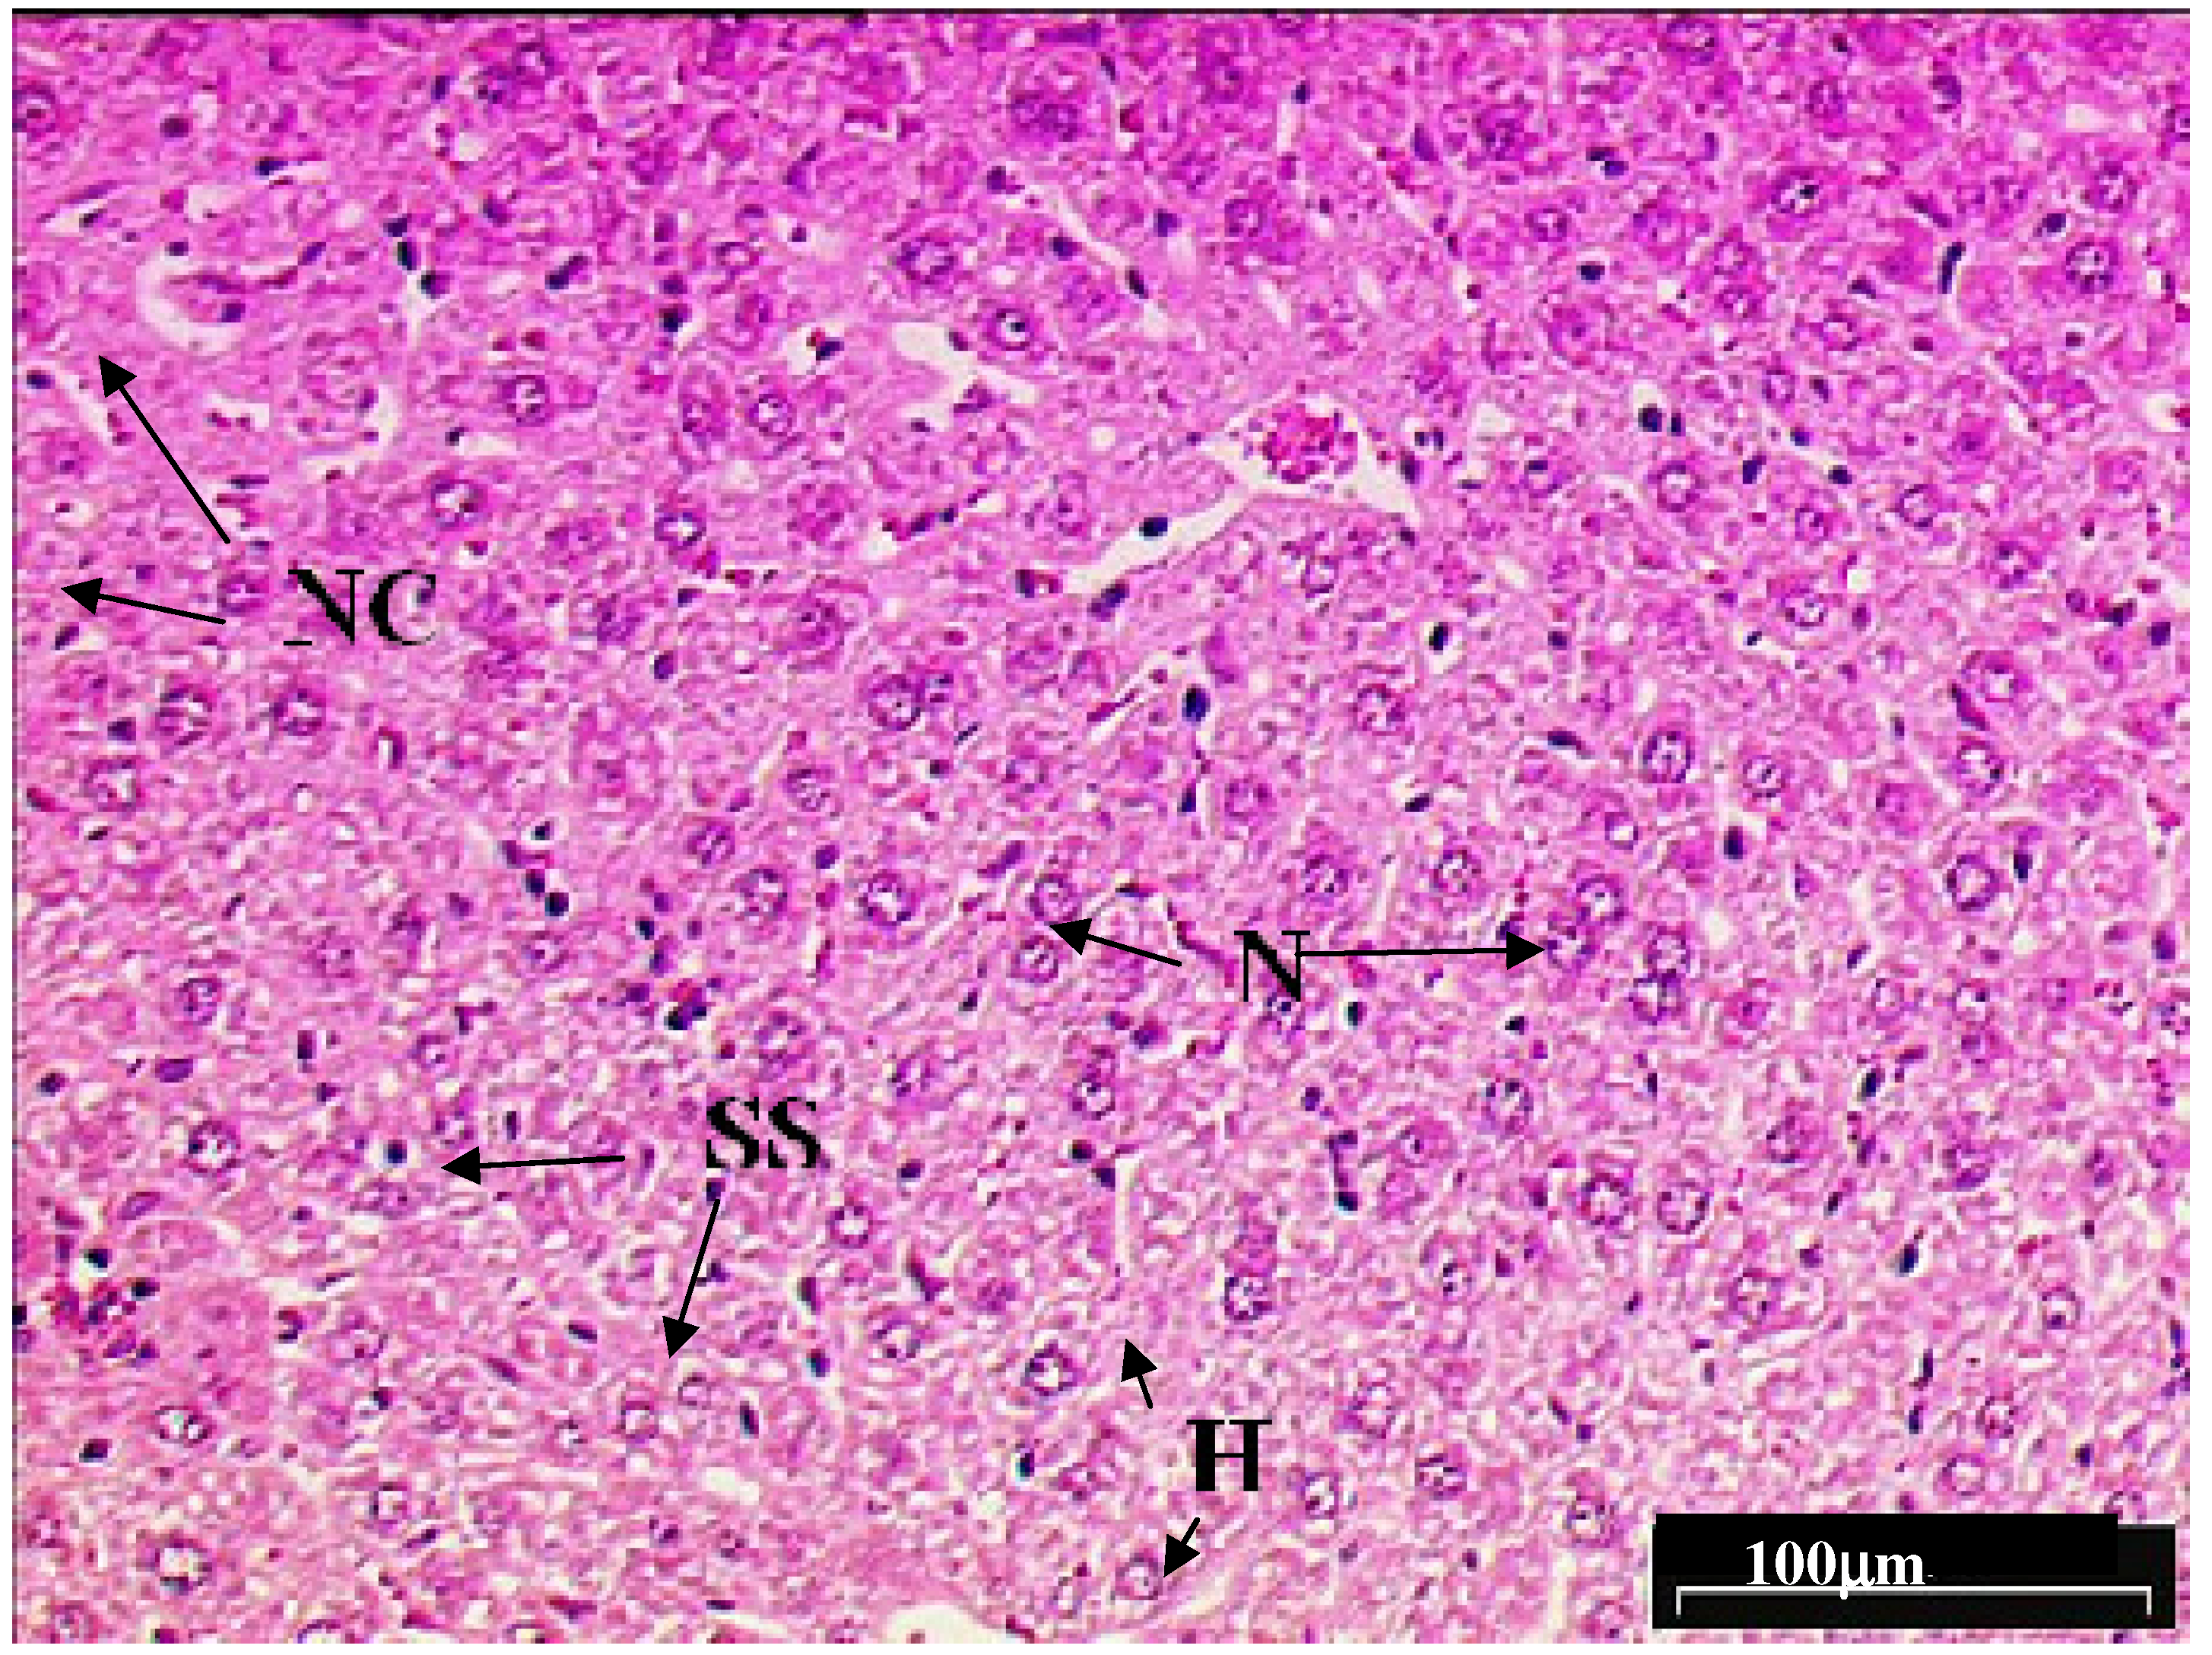

2.3. Hepatoprotective activity of L. edodes methanolic extract